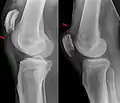

X-ray of a tear of the patellar tendon. On the left: The kneecap is pulled up. On the right: Significant dent in the soft tissue above the kneecap. -